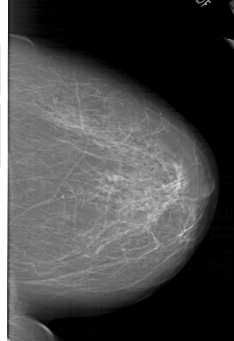

A_1952_1.RIGHT_MLO

RIGHT_MLO LINES 6481 PIXELS_PER_LINE 4096 BITS_PER_PIXEL 12 RESOLUTION 43.5 NON_OVERLAY